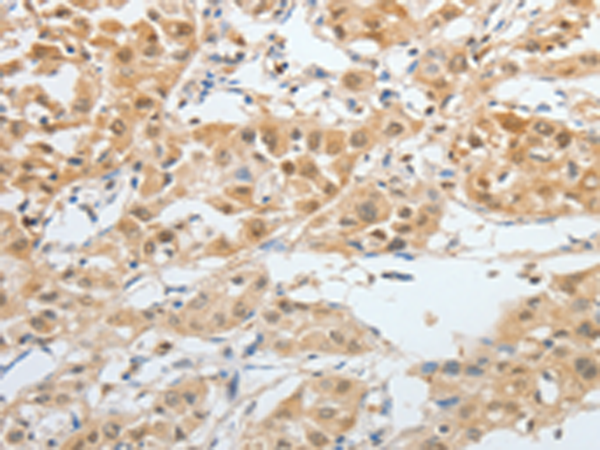

分类: 科研抗体货号: P11003别名: RYA3, LPLUNC3, C20orf185, dJ726C3.4应用: WB,IHC反应种属: Human